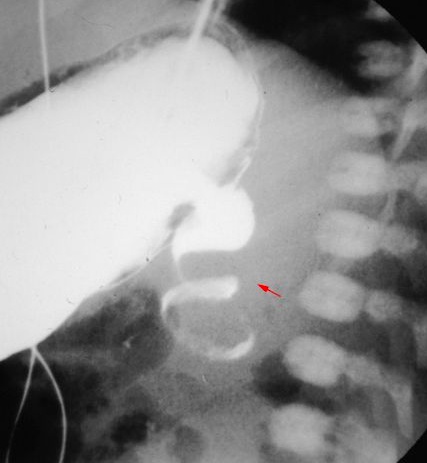

The classic radiographic sign associated with duodenal atresia is the “double bubble” sign on abdominal radiography.

The double bubble is denoted the higher, larger, left-sided stomach bubble together with the lower, smaller, right-sided bubble of the dilated proximal duodenum.

corkscrew appearance (white arrow)